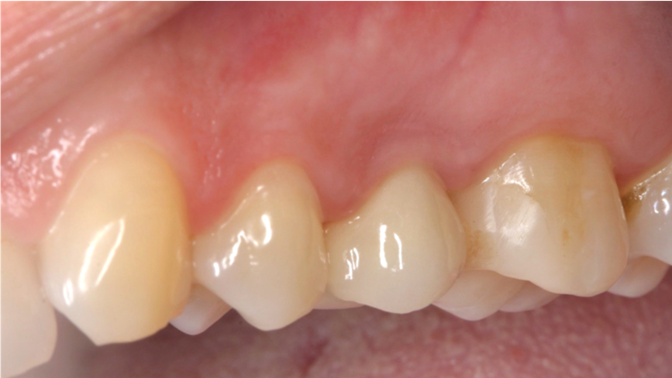

Clinical case: Extraction, immediate implant placement, & provisionalization

- Courtesy of Dr. Iulian Filipov, Romania -

AnyRidge, R2GATE, guided surgery, immediate placement, immediate provisionalization, initial stability, Dr. Iulian Filipov, #25, maxillary posterior, immediate loading, Mega ISQ

Products:

AnyRidge implant system, R2GATE, MEGA ISQ, Digital prosthesis